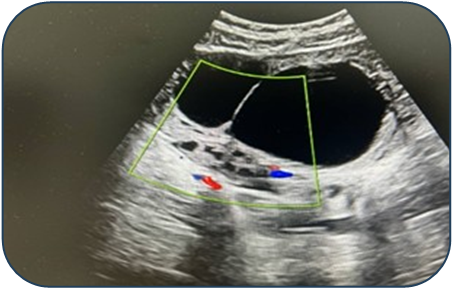

Case 1: A 17-year-old female presented with acute pain. Ultrasound revealed a 95 mm complex left ovarian cyst with no Doppler flow (Fig. 1). Emergency laparoscopy confirmed a 720-degree torsion. Detorsion and cystectomy were performed. Intraoperative findings are shown in Fig. 2, Fig. 3, and Fig. 4. Histopathology reported a serous cystadenoma. Postoperative ultrasound on day 5 confirmed a viable ovary (Fig. 5). | Figure 1. Ultrasound findings of a left ovarian cyst with torsion |

Case 2: An 11-year-old female presented with a torsed, edematous left ovary (69x49 mm) on ultrasound (Fig. 6). Laparoscopic detorsion alone was performed (Fig. 7 & Fig. 8). Serial postoperative ultrasounds documented the gradual resolution of edema and the return of vascularity by day 20 (Fig. 9), confirming ovarian recovery. | Figure 6. Preoperative ultrasound examination of the left ovary |